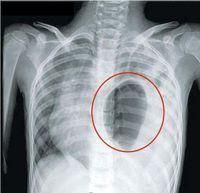

(8)滲出性胸膜炎:左下胸和左上腹明顯疼痛,左側胸呼吸音減弱,叩診濁音,X檢查示:左側胸腔積液,但胸部仔細聽診可聞及腸鳴,鋇餐檢查可發現胸內有充鋇的腸攀影。

(9)左側氣胸:心臟右移、心音遠弱,左上胸叩診呈鼓音,下胸叩診呈濁音, 語顫減弱,呼吸音減弱,胸透為左胸腔有氣液征,根據胸腔內有氣液徵象,可與氣胸進行鑑別。叩診呈鼓音、語顫減弱、呼吸音減弱的區域多為胃疝入胸腔呈倒置的葫蘆狀,胃內充滿氣體致胃體極度擴大所致。

一、疾病症狀下胸部及上腹腔部尤其季肋部的開放性外傷或嚴重鈍傷,出現以下情況應考慮膈肌損傷及膈疝形成:1.出現胸悶、氣促合併噁心、嘔吐等消化道症狀;2.胸外傷後出現明顯腹膜刺激征,腹穿抽出不凝血;對有胸部外傷史而出現機械性的腸梗阻,要想到有創傷性膈疝的可能;3.腹部外傷後出現呼吸困難,縱膈移位,呼吸音低或消失,而無明顯的肺損傷;4.急性鈍性胸腹部閉合性損傷後出現舟狀腹;5.胸部或上腹部閉合性損傷後,一側胸痛並向同側肩部放射是膈肌損傷的典型症狀;6.胸腔聞及腸鳴音;7.胸腔閉式引流或胸穿抽得消化道物如胃腸液、食物殘渣等,並聞到臭味者。二、輔助檢查1.床旁B超:急診床旁B超因為簡便易行、無創,可首先進行。2.胸部X線及CT檢查:最重要的檢查手段。3.螺鏇cT:對膈肌損傷診斷的價值最高,敏感性達71%,特異性100%。4.胸腹部CT檢查:應一次連續掃查,這樣不但可以顯膈肌裂傷,而且可以判斷胸腹腔臟器有無移位,以明確診斷。5.手術探查:對於通過輔助檢查不能確診而又高度懷疑本病者,應儘早手術探查。胸腹傷需開胸或剖腹時,應常規檢查膈肌,以免漏診。如條件允許,採用胸腔鏡或腹腔鏡檢查確診率可達100%。